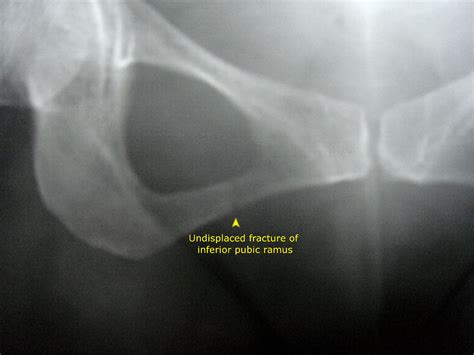

Diagnosing a Ramus Pubic Fracture involves a combination of physical examination and imaging tests. The diagnostic process typically includes:

• Physical Examination: A healthcare provider will assess the pelvic area for pain, swelling, and deformity.

• Imaging Tests: X-rays, CT scans, and MRI scans are commonly used to visualize the fracture and determine its extent.

In some cases, additional tests may be required to rule out other injuries or complications.